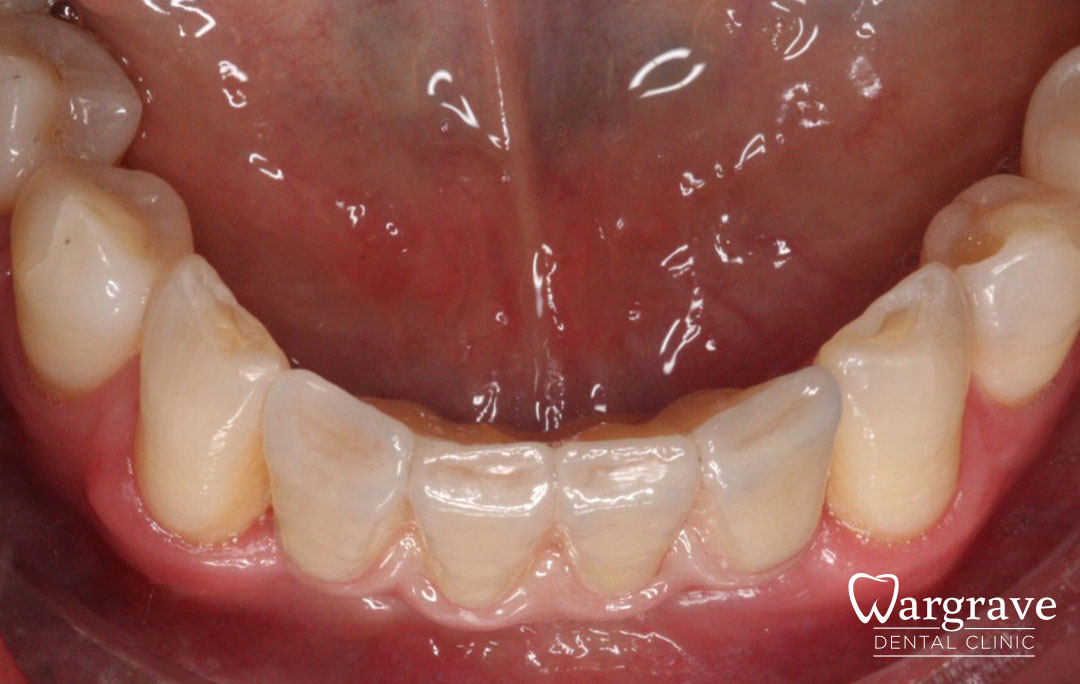

Healthy Smiles These are more advanced examples of different treatments available.All cases shown were carried out by Dr R Khurana unless otherwise stated. Immediate implants Anterior Mandible Bone Regeneration Anterior Mandibular Implant Bridge Maxillary Anterior Implant Bridge Implant stabilised ‘Life Like’ replacement dentures Implant Bridge after 10-years with zero bone loss Implant examples including ZBLC concepts Adhesive Bridge solution for a missing premolar Multidisciplinary care Orthodontics, Replacement veneers and composite bonding Adhesive Bridge solution for missing central incisors Replacement crown, Veneer and Composite Bonding Replacement Crowns and Veneer Injection Moulding using Composite Resin Equilibration Tooth Whitening to treat Developmental Discolouration